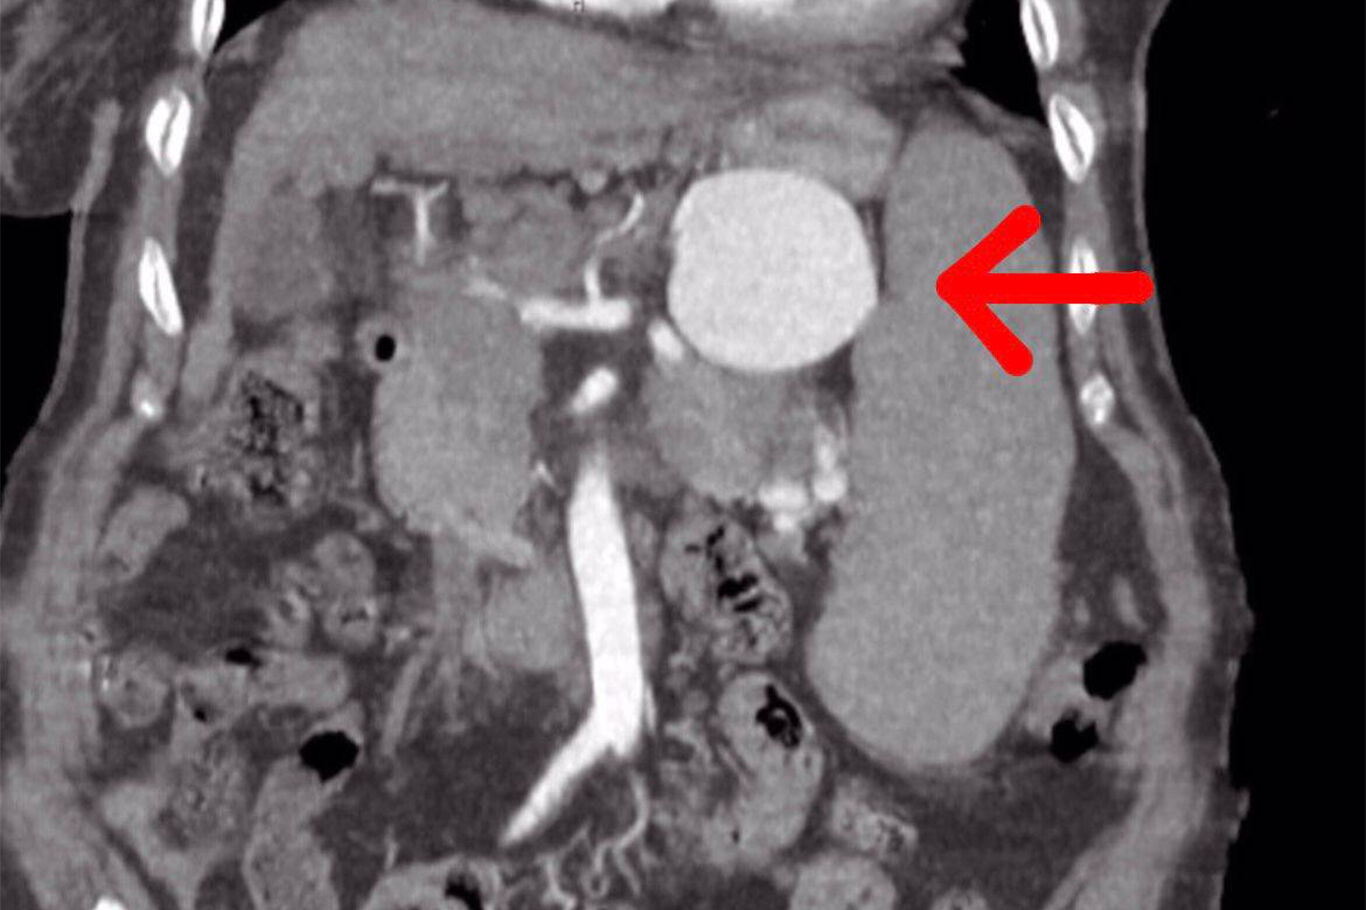

dalak-damarinda-7-cm-baloncuk-olusan-75-yasindaki-hasta-basarili-ameliyat-ile-sagligina-kavustu-15d1e893

dalak-damarinda-7-cm-baloncuk-olusan-75-yasindaki-hasta-basarili-ameliyat-ile-sagligina-kavustu-78258d0e

dalak-damarinda-7-cm-baloncuk-olusan-75-yasindaki-hasta-basarili-ameliyat-ile-sagligina-kavustu-54596dc3

dalak-damarinda-7-cm-baloncuk-olusan-75-yasindaki-hasta-basarili-ameliyat-ile-sagligina-kavustu-c83ff761

dalak-damarinda-7-cm-baloncuk-olusan-75-yasindaki-hasta-basarili-ameliyat-ile-sagligina-kavustu-35d7655a

dalak-damarinda-7-cm-baloncuk-olusan-75-yasindaki-hasta-basarili-ameliyat-ile-sagligina-kavustu-d6745506